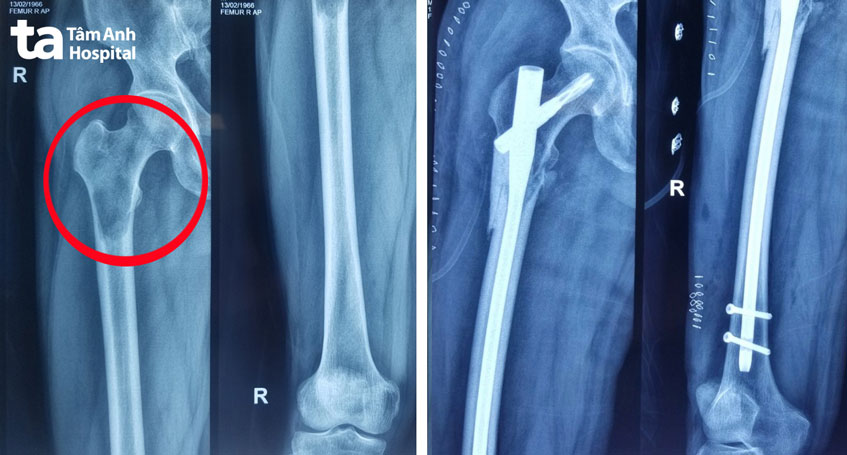

TS.BS Văn Đức Minh Lý, Trung tâm Chấn thương Chỉnh hình, cho biết người bệnh bị ung thư xương di căn (u xương ác tính) ở đầu trên xương đùi phải. Tình trạng này xảy ra khi các tế bào ung thư từ thận (ổ nguyên phát) di căn tới tổ chức xương, gây tổn hại tới cấu trúc của xương. Đây là biến chứng di căn của ung thư thận giai đoạn cuối.

Đầu trên xương đùi phải là vị trí chịu lực lớn khi cơ thể vận động. Ở trường hợp của ông Tài, ⅔ chu vi của đầu trên xương đùi phải đã bị hủy nên người bệnh đối mặt với nguy cơ gãy xương rất cao. Chỉ cần những động tác như với tay lấy đồ hoặc bước hụt chân cũng có thể làm gãy ngang xương đùi. Hậu quả là người bệnh phải nằm một chỗ, không thể tự di chuyển, gây khó khăn cho việc điều trị ung thư và có thể làm phát sinh các biến chứng do nằm lâu như loét tì đè, teo cơ…

Ngoài ra, nếu để xương gãy mới điều trị thì quá trình phẫu thuật sẽ gặp nhiều khó khăn hơn do hai đầu xương gãy có thể vỡ nát hoặc di lệch… Vì vậy, người bệnh được chỉ định phẫu thuật kết hợp xương, dự phòng gãy xương bệnh lý. Bác sĩ đóng đinh nội tủy vào lòng xương đùi phải để giữ khung xương, sau đó dùng xi măng sinh học gia cố, tạo hình lại phần xương đã mất đi. Nhờ đó, xương đùi phải của người bệnh vững chắc và chịu lực tốt hơn, giảm đáng kể nguy cơ gãy xương.